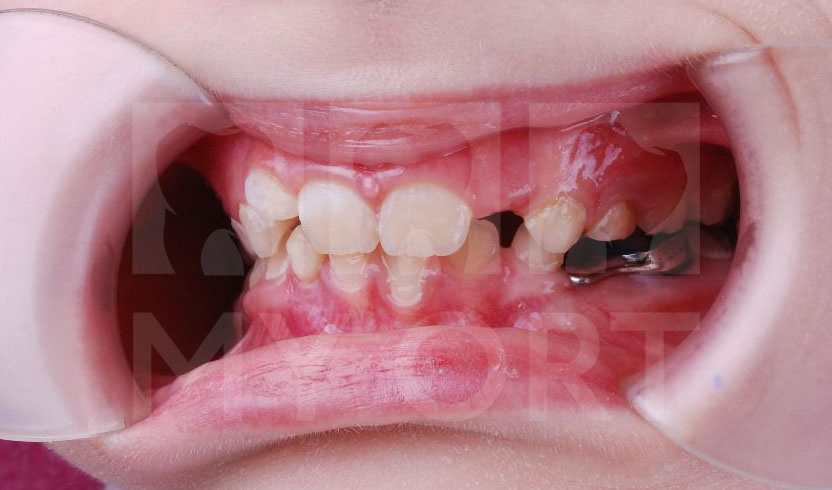

Родители семилетней девочки обратились ко мне, врачу-стоматологу, ортодонту, гнатологу, с жалобами на неправильный прикус. У ребенка начали прорезываться постоянные зубы и родителей беспокоило отсутствие места для нормального роста зубов.

Компьютерная томография (КТ) показала у ребенка — дистальный прикус, ретрузию и кант окклюзионной плоскости зубов.

Улыбка До и После

Посмотрите, что у нас получилось:

До и после